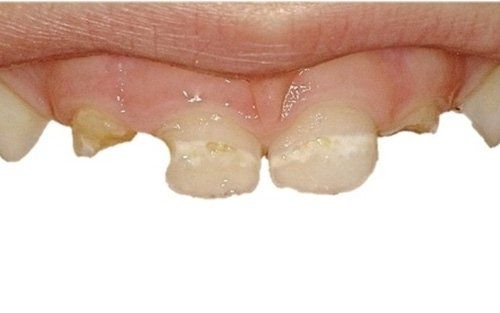

La carie nel bambino è una delle principali cause, insieme all’ortodonzia, di richiesta di intervento del dentista. La patologia ha una evoluzione particolarmente rapida in virtù della scarsità di smalto a difesa del dente da latte. Ciò comporta che, dal momento in cui il dente si ammala a quello in cui ne viene coinvolta la polpa (ovvero il nervo), il tempo sia veramente poco (vedi anche endodonzia pediatrica).

Spesso i dentini da latte cominciano a cariarsi già appena erompono nel cavo orale in quanto sono frequentemente a contatto con zuccheri semplici, come quelli veicolati dal biberon. Particolarmente aggressivi per i denti da latte risultano: tutte le tisane/infusi in commercio in bustine già pronte e pre-zuccherate; il latte zuccherato con qualsivoglia tipologia, incluso il miele; il latte e biscotti, specie nell’uso notturno; l’utilizzo quotidiano, spesso al posto dell’acqua, di succhi di frutta o bevande acide, per citare alcuni fra i più comuni errori commessi nel tentativo di dare una alimentazione completa al bambino, che spesso si traduce nella comparsa di una patologia chiamata